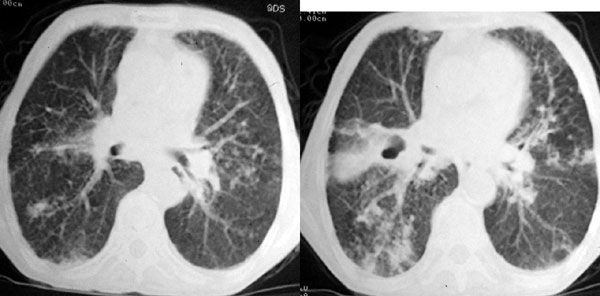

f 76 间断咳嗽 咳痰1年余 发热不明显 身体削瘦

1、右肺中叶近肺门区可见一空洞样病灶,内壁不规则,有与邻近支气管相通的征象,其外侧大片肺组织软组织状实变,余肺可见散在点、片絮状密度增高影,肺纹理可见明显增粗及串珠样改变;

1、右侧中央型(空洞性)肺癌并双肺受累(包括转移、阻塞性炎症、癌性淋巴管炎);纵隔、右侧腋窝内淋巴结肿大、转移;右侧胸膜增厚粘连,胸腔少量积液;

1、两肺结核,并右肺下叶干酪性肺炎及空洞形成,建议支气管镜检查,除外新生物。

诊断意见:1、右侧中央型肺癌并肺内胸膜转移;2、双肺广泛间质纤维化。

鉴别诊断:肺结核。